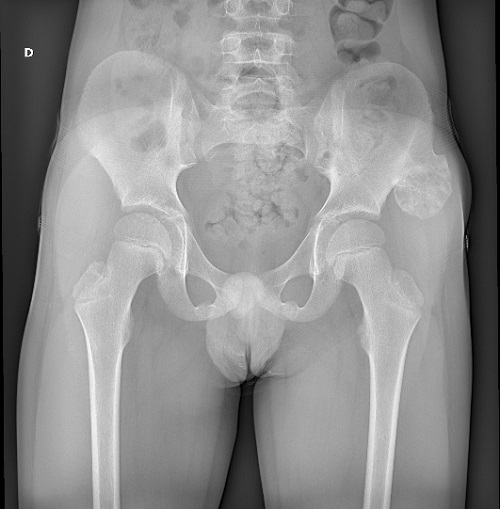

Se realiza TAC de pelvis: lesión exostósica con continuidad cortical y medular a nivel de la cresta ilíaca izquierda, con base de implantación ancha, compatible con lesión osteocondromatosa sésil. Medidas de 42 x 32 mm. Se reconoce un capuchón cartilaginoso de aproximadamente 5 mm.

• Adecuada congruencia articular coxofemoral.

• La esfericidad de las cabezas femorales se encuentra respetada.

• Las estructuras musculotendinosas presentan continuidad anatómica y señal conservada.

• La articulación pubiana y ambas articulaciones sacroilíacas no presentan alteraciones.